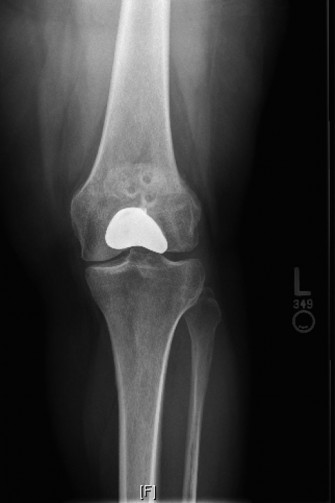

A 48-year-old female patient presents with anterior left knee pain. She has had a history of recurrent patell…